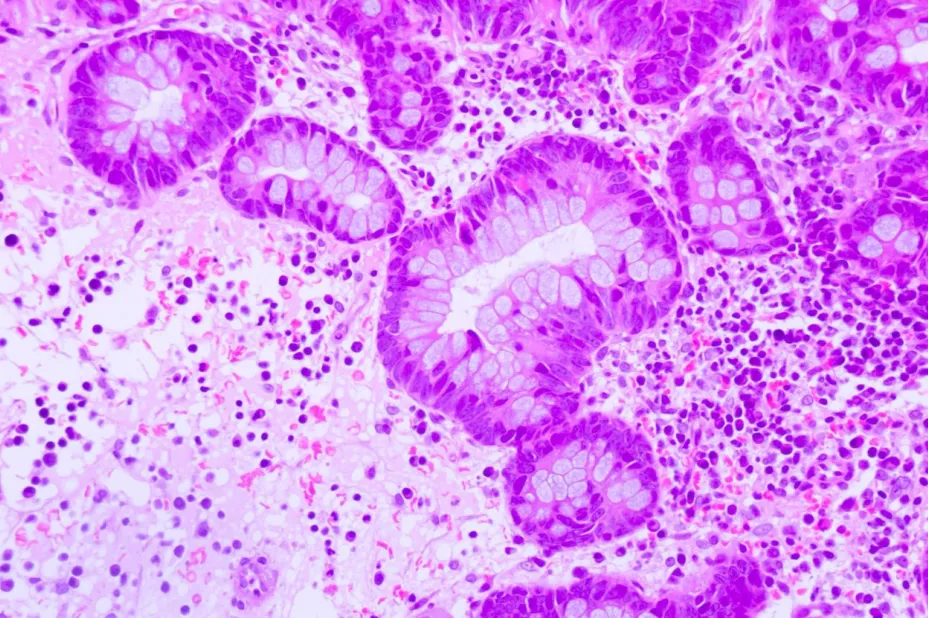

Estas nuevas indicaciones terapéuticas derivadas de los estudios PAPILLON, MARIPOSA-2 y MARIPOSA han respaldado la eficacia de combinaciones de amivantamab con otros fármacos como lazertinib o con quimioterapia como tratamientos de primera línea para pacientes con cáncer de pulmón no microcítico (CPNM) avanzado con mutaciones específicas.

Gracias a estas aprobaciones se podrá beneficiar a pacientes con cáncer de pulmón de células no pequeñas (CPCNP) con inserción Exon20 en primera línea y a pacientes con mutaciones comunes de EGFR en segunda línea, lo que brindará esperanza a personas que necesitan nuevas combinaciones de fármacos para tener una mejor respuesta, frenar la progresión de la enfermedad y lograr una tendencia favorable en la supervivencia de los pacientes.

“Existen muchas mutaciones en el cáncer de pulmón que se pueden tratar, y las alteraciones en el gen EGFR son de las más comunes y difíciles de manejar. Identificar a los pacientes con CPNM avanzado causado por estas mutaciones y ofrecerles tratamientos específicos desde el principio, como la combinación de fármacos, puede ser clave para cubrir estas necesidades médicas urgentes y hasta el momento no satisfechas”, aseguró el Dr. Alatorre.